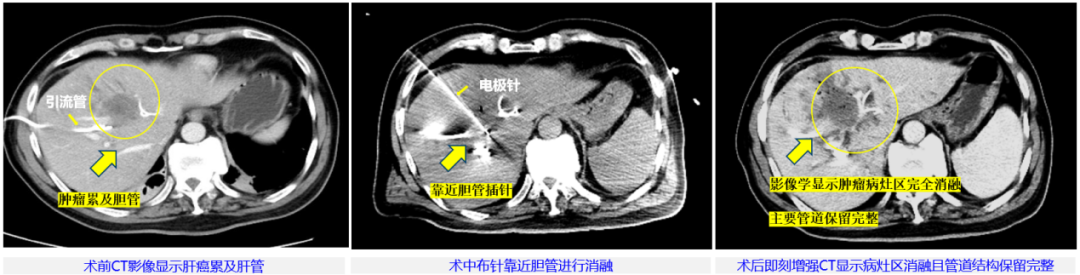

本次治疗病例为57岁男性,临床诊断肝内胆管细胞癌局部转移,侵犯肝门伴梗阻性黄疸,主病灶45mm×36mm,已行双侧PTBD(经皮经肝胆管穿刺引流术)减黄处理。由于病灶位于肝门部,紧邻左侧门静脉及胆囊,这里密布肝动脉、门静脉和胆管等重要脉管结构,无法进行手术切除根治,也不适合各种冷/热消融治疗。董家鸿牵头肝胆胰中心多学科讨论后决定,为患者进行具有脉管保护优势的“微纳刀”消融治疗。

整个手术过程中,患者行局部麻醉,在B超联合CT引导下使用“微纳刀”通过单针对病灶区进行消融,消融过程历时15分钟。术中未使用任何肌松剂,也没有采用气管麻醉,患者始终处于清醒状态,可与医生交流。脉冲施加过程中未见肌肉有明显收缩反应,患者也无明显的疼痛感觉,术后即刻增强CT复查发现,肿瘤病灶区在影像学上已显示全部消融,邻近胆管、血管未见损伤。随后患者安全返回病房,术中术后生命体征平稳、未发现不良反应。